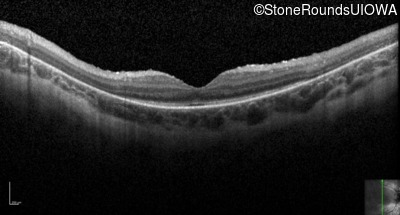

Optical Coherence Tomography - Right - 10/100 -1 sc

Exemplar / OCT Stack